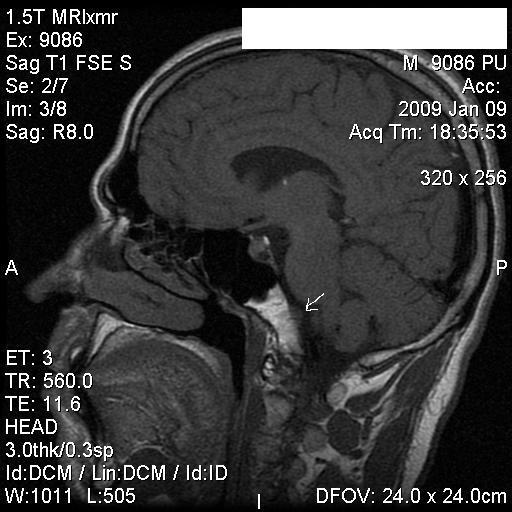

Хордома (МРТ)

Хордома (Chordoma) - редкая опухоль, происходящая из остатков хорды эмбриона. Характерными местами ее развития являются основание черепа и область крестца.